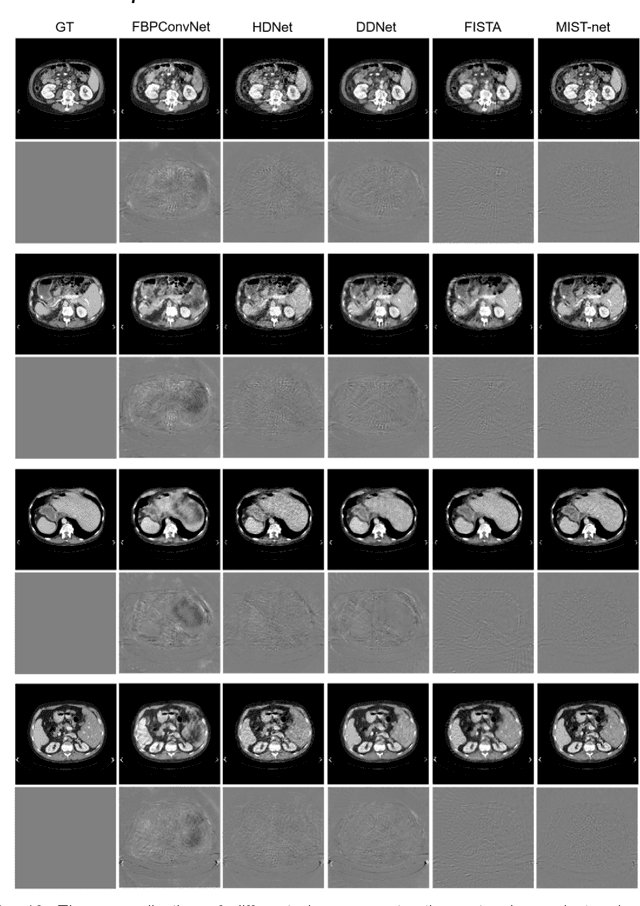

Abstract:The deep learning-based tomographic image reconstruction methods have been attracting much attention among these years. The sparse-view data reconstruction is one of typical underdetermined inverse problems, how to reconstruct high-quality CT images from dozens of projections is still a challenge in practice. To address this challenge, in this article we proposed a Multi-domain Integrative Swin Transformer network (MIST-net). First, the proposed MIST-net incorporated lavish domain features from data, residual-data, image, and residual-image using flexible network architectures. Here, the residual-data and residual-image domains network components can be considered as data consistency module to eliminate interpolation errors in both residual data and image domains, and then further retain image details. Second, to detect image features and further protect image edge, the trainable edge enhancement filter was incorporated into sub-network to improve encode-decode ability. Third, with classical Swin Transformer, we further designed a high-quality reconstruction transformer (i.e., Recformer) to improve reconstruction performance. Recformer inherited the power of Swin transformer to capture global and local features of reconstructed image. The experiments on numerical datasets with 48 views demonstrated our proposed MIST-net provided higher reconstructed image quality with small feature recovery and edge protection than other competitors including advanced unrolled networks. The trained network was transferred to real cardiac CT dataset to further validate the advantages as well as good robustness of our MIST-net in clinical applications.